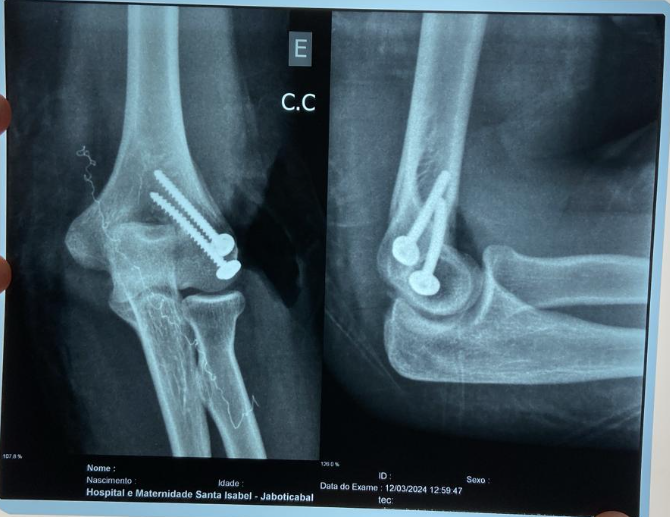

Na terça-feira (2), a UPA de Bebedouro e a Secretaria Municipal de Saúde terminaram as apurações da Sindicância aberta para investigar falha no atendimento a paciente, vítima de acidente de trânsito, conforme publicado pela Gazeta na edição 10.829, de 16 de março. A conclusão foi pelo desligamento do médico que atendeu a paciente e não adotou os protocolos adequados, como acionamento do ortopedista de plantão.